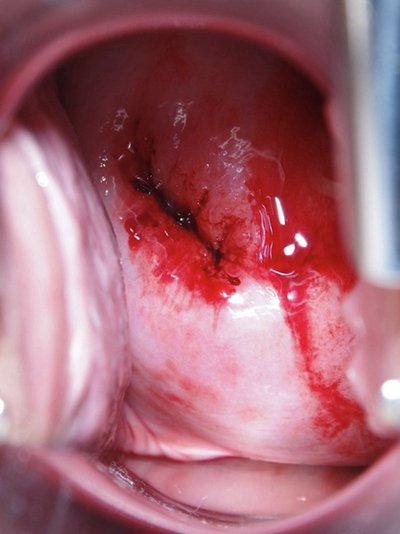

子宮頸糜爛圖片

宮頸糜爛 (8)

宮頸糜爛 (9)

宮頸糜爛 (56)

宮頸糜爛 (57)

宮頸糜爛 (58)

宮頸糜爛 (59)

宮頸糜爛 (6)

宮頸糜爛 (60)

宮頸糜爛 (7)